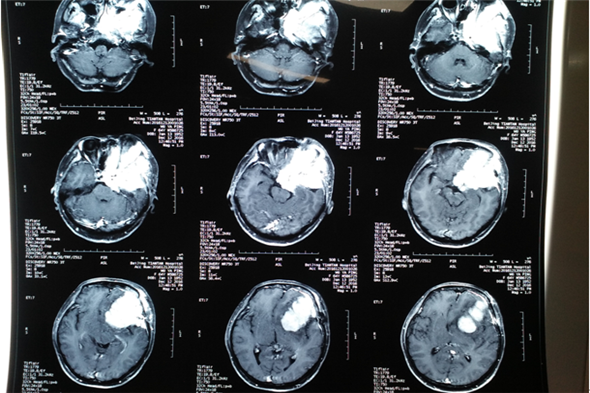

1月7日,麻醉医生顺利麻醉,手术室护士密切配合,手术由神经外二科吴卫东主任主刀,吴主任凭借精湛的手术技能,术中探寻蝶骨脊、颞骨岩部及斜坡处,行电烧并切断供血。手术中,由于患者病情重,骨质受侵蚀,酥脆明显,导致出血较多。吴主任当机立断,切断根部后再于显微镜下寻找到边界逐步分离并分块切除肿瘤组织,由于肿瘤长度达9cm,前方达前颅窝底,内侧达右侧蝶骨脊,后方达颞极下部,并在眶后壁切除了部分肿瘤组织,根据肿瘤颜色及质地以及侵蚀程度考虑恶性脑膜瘤可能性大。手术进行的很顺利,术后第一天患者即意识清醒,无功能缺失。如此喜人的结果,令所有神经外二科的医护人员倍感欣慰。

术后第一天CT